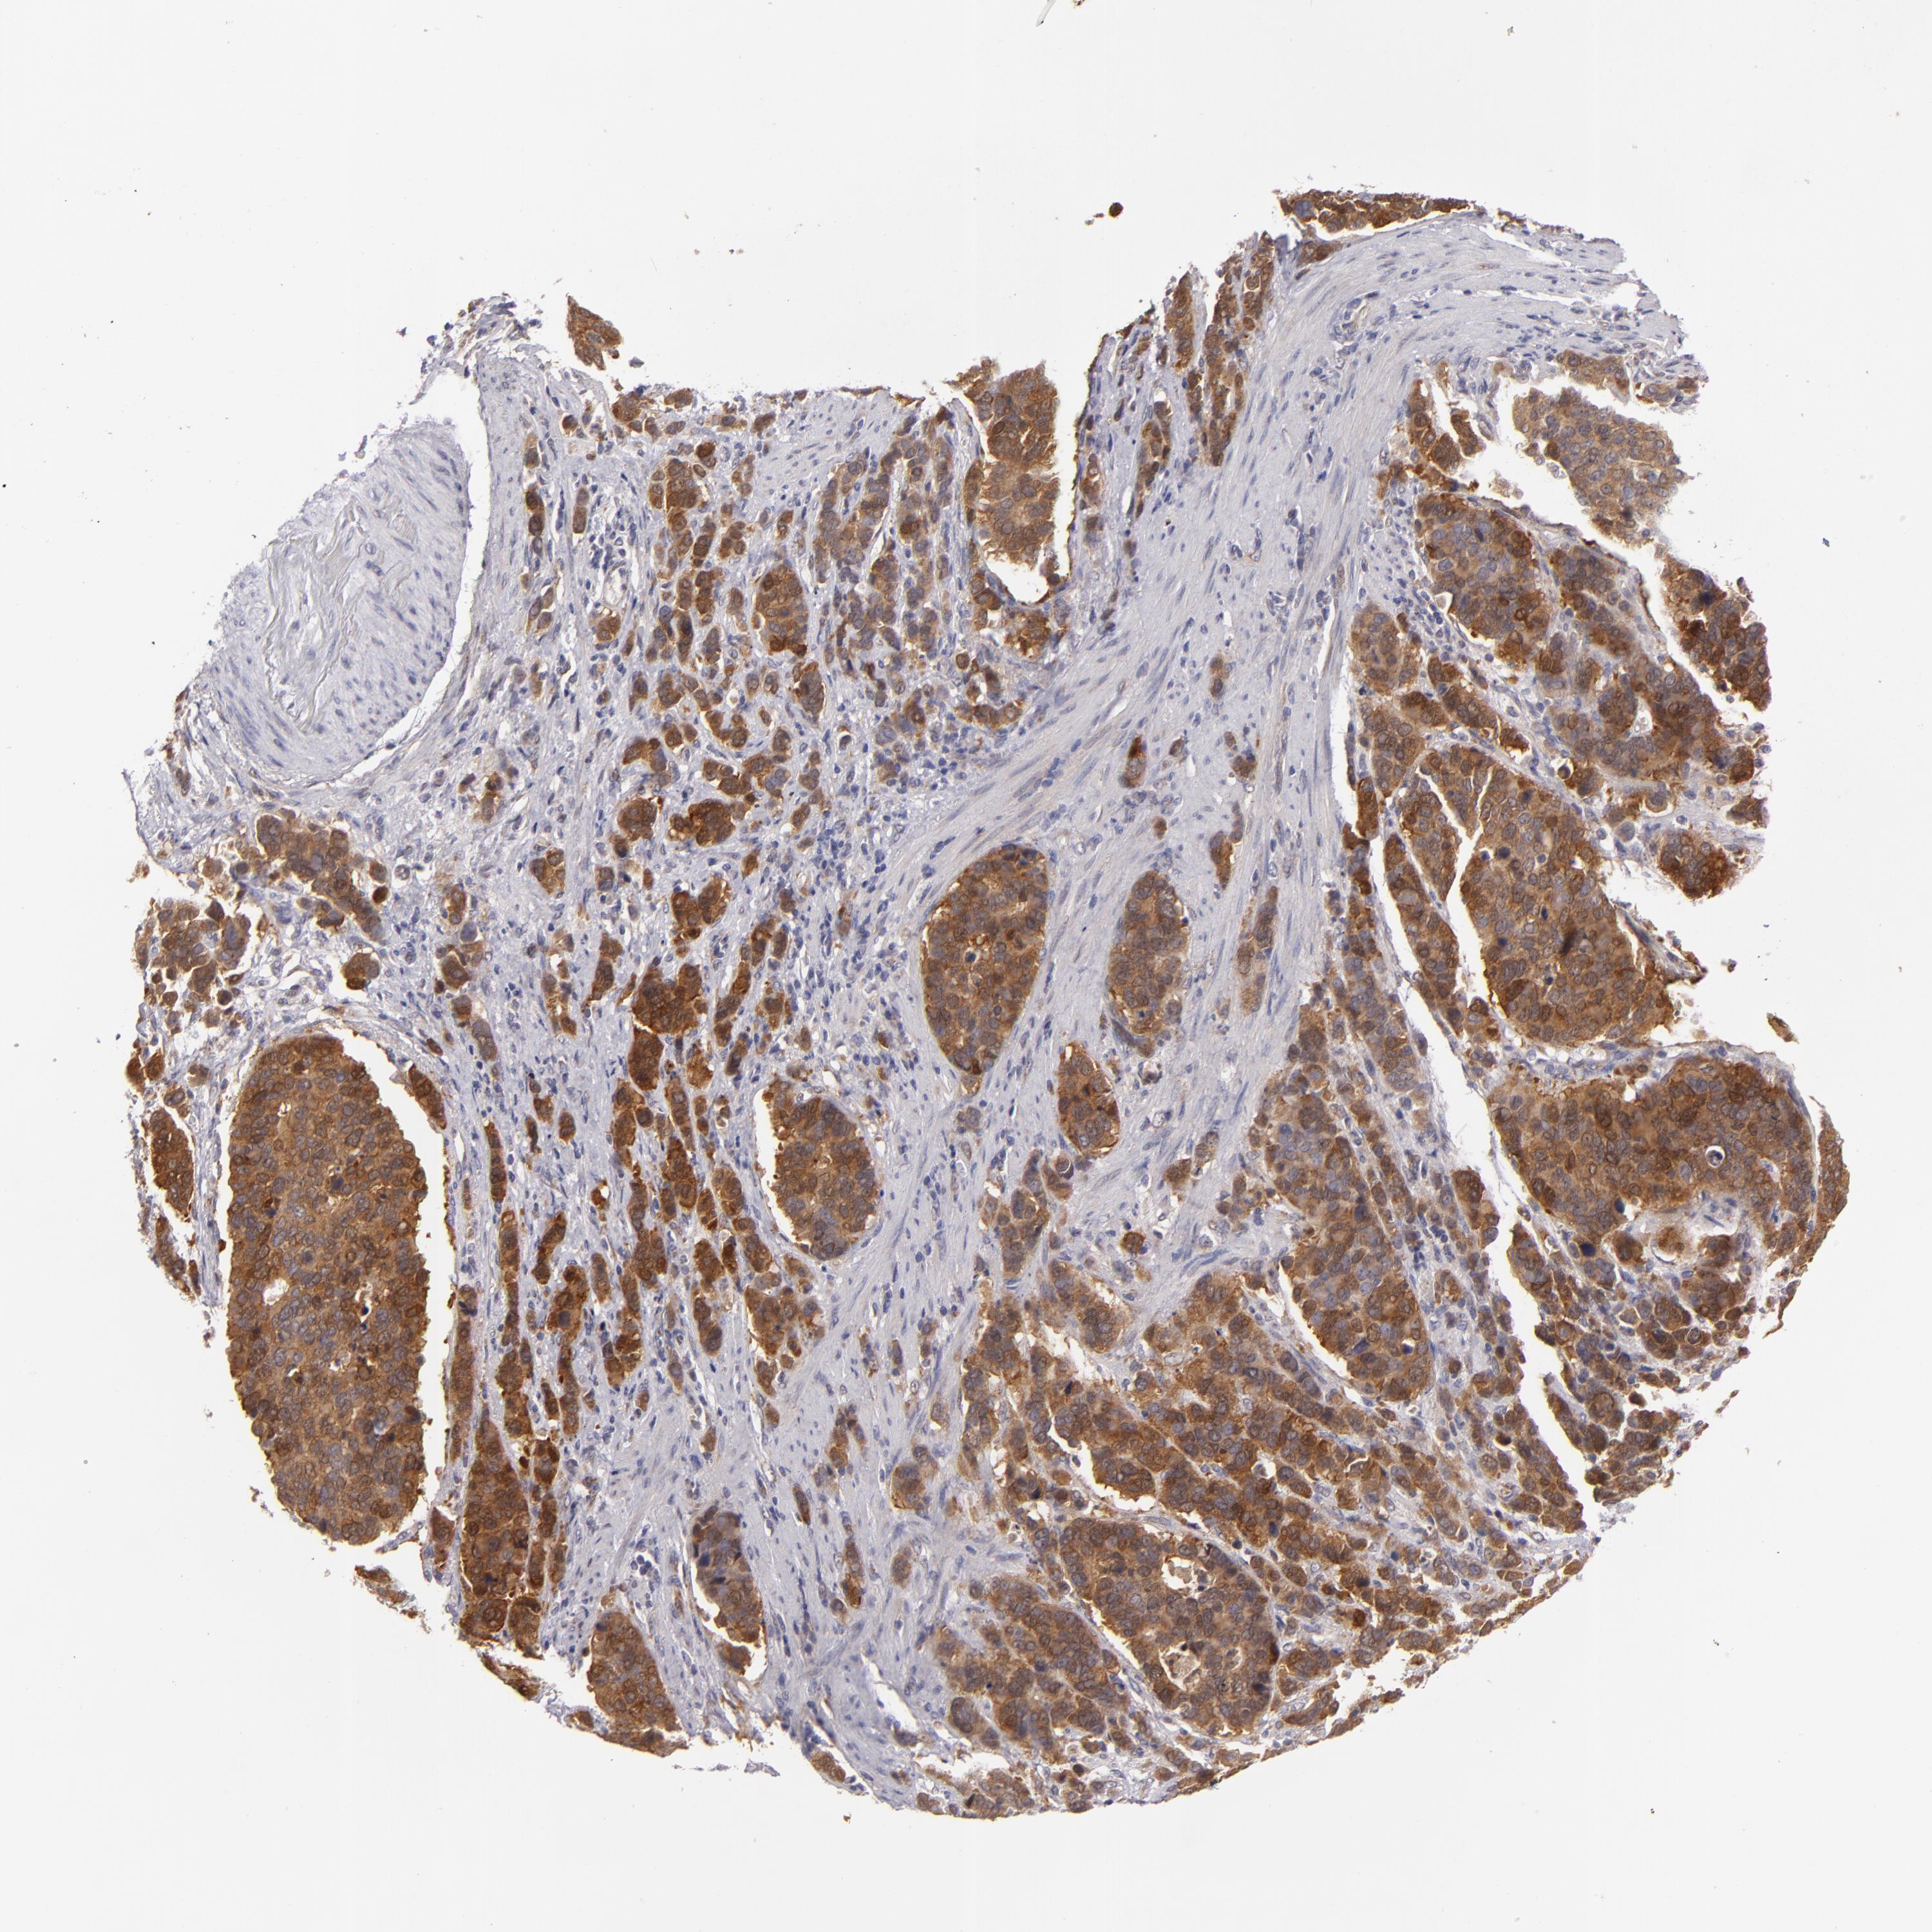

STOMACH CANCER - Protein expressioni

A mouse-over function shows sample information and annotation data. Click on an image to view it in a full screen mode. Samples can be filtered based on level of antibody staining by selecting one or several of the following categories: high, medium, low and not detected. The assay and annotation is described here.

Note that samples used for immunohistochemistry by the Human Protein Atlas do not correspond to samples in the TCGA dataset.

Antibody stainingi

Antibody staining in the annotated cell types in the current human tissue is reported as not detected, low, medium, or high, based on conventional immunohistochemistry profiling in selected tissues. This score is based on the combination of the staining intensity and fraction of stained cells.

Each image is clickable and will lead to virtual microscopy that enables deeper exploration of all samples and also displays staining intensity scores, fraction scores and subcellular localization as well as patient and tissue information for each sample.

Antibody HPA001871

Antibody HPA001919

Staining

High

Medium

Low

Not detected

Intensity

Strong

Moderate

Weak

Negative

Quantity

>75%

75%-25%

<25%

None

Location

Nuclear

Cytoplasmic/membranous

Cytoplasmic/membranous,nuclear

Adenocarcinoma, NOS